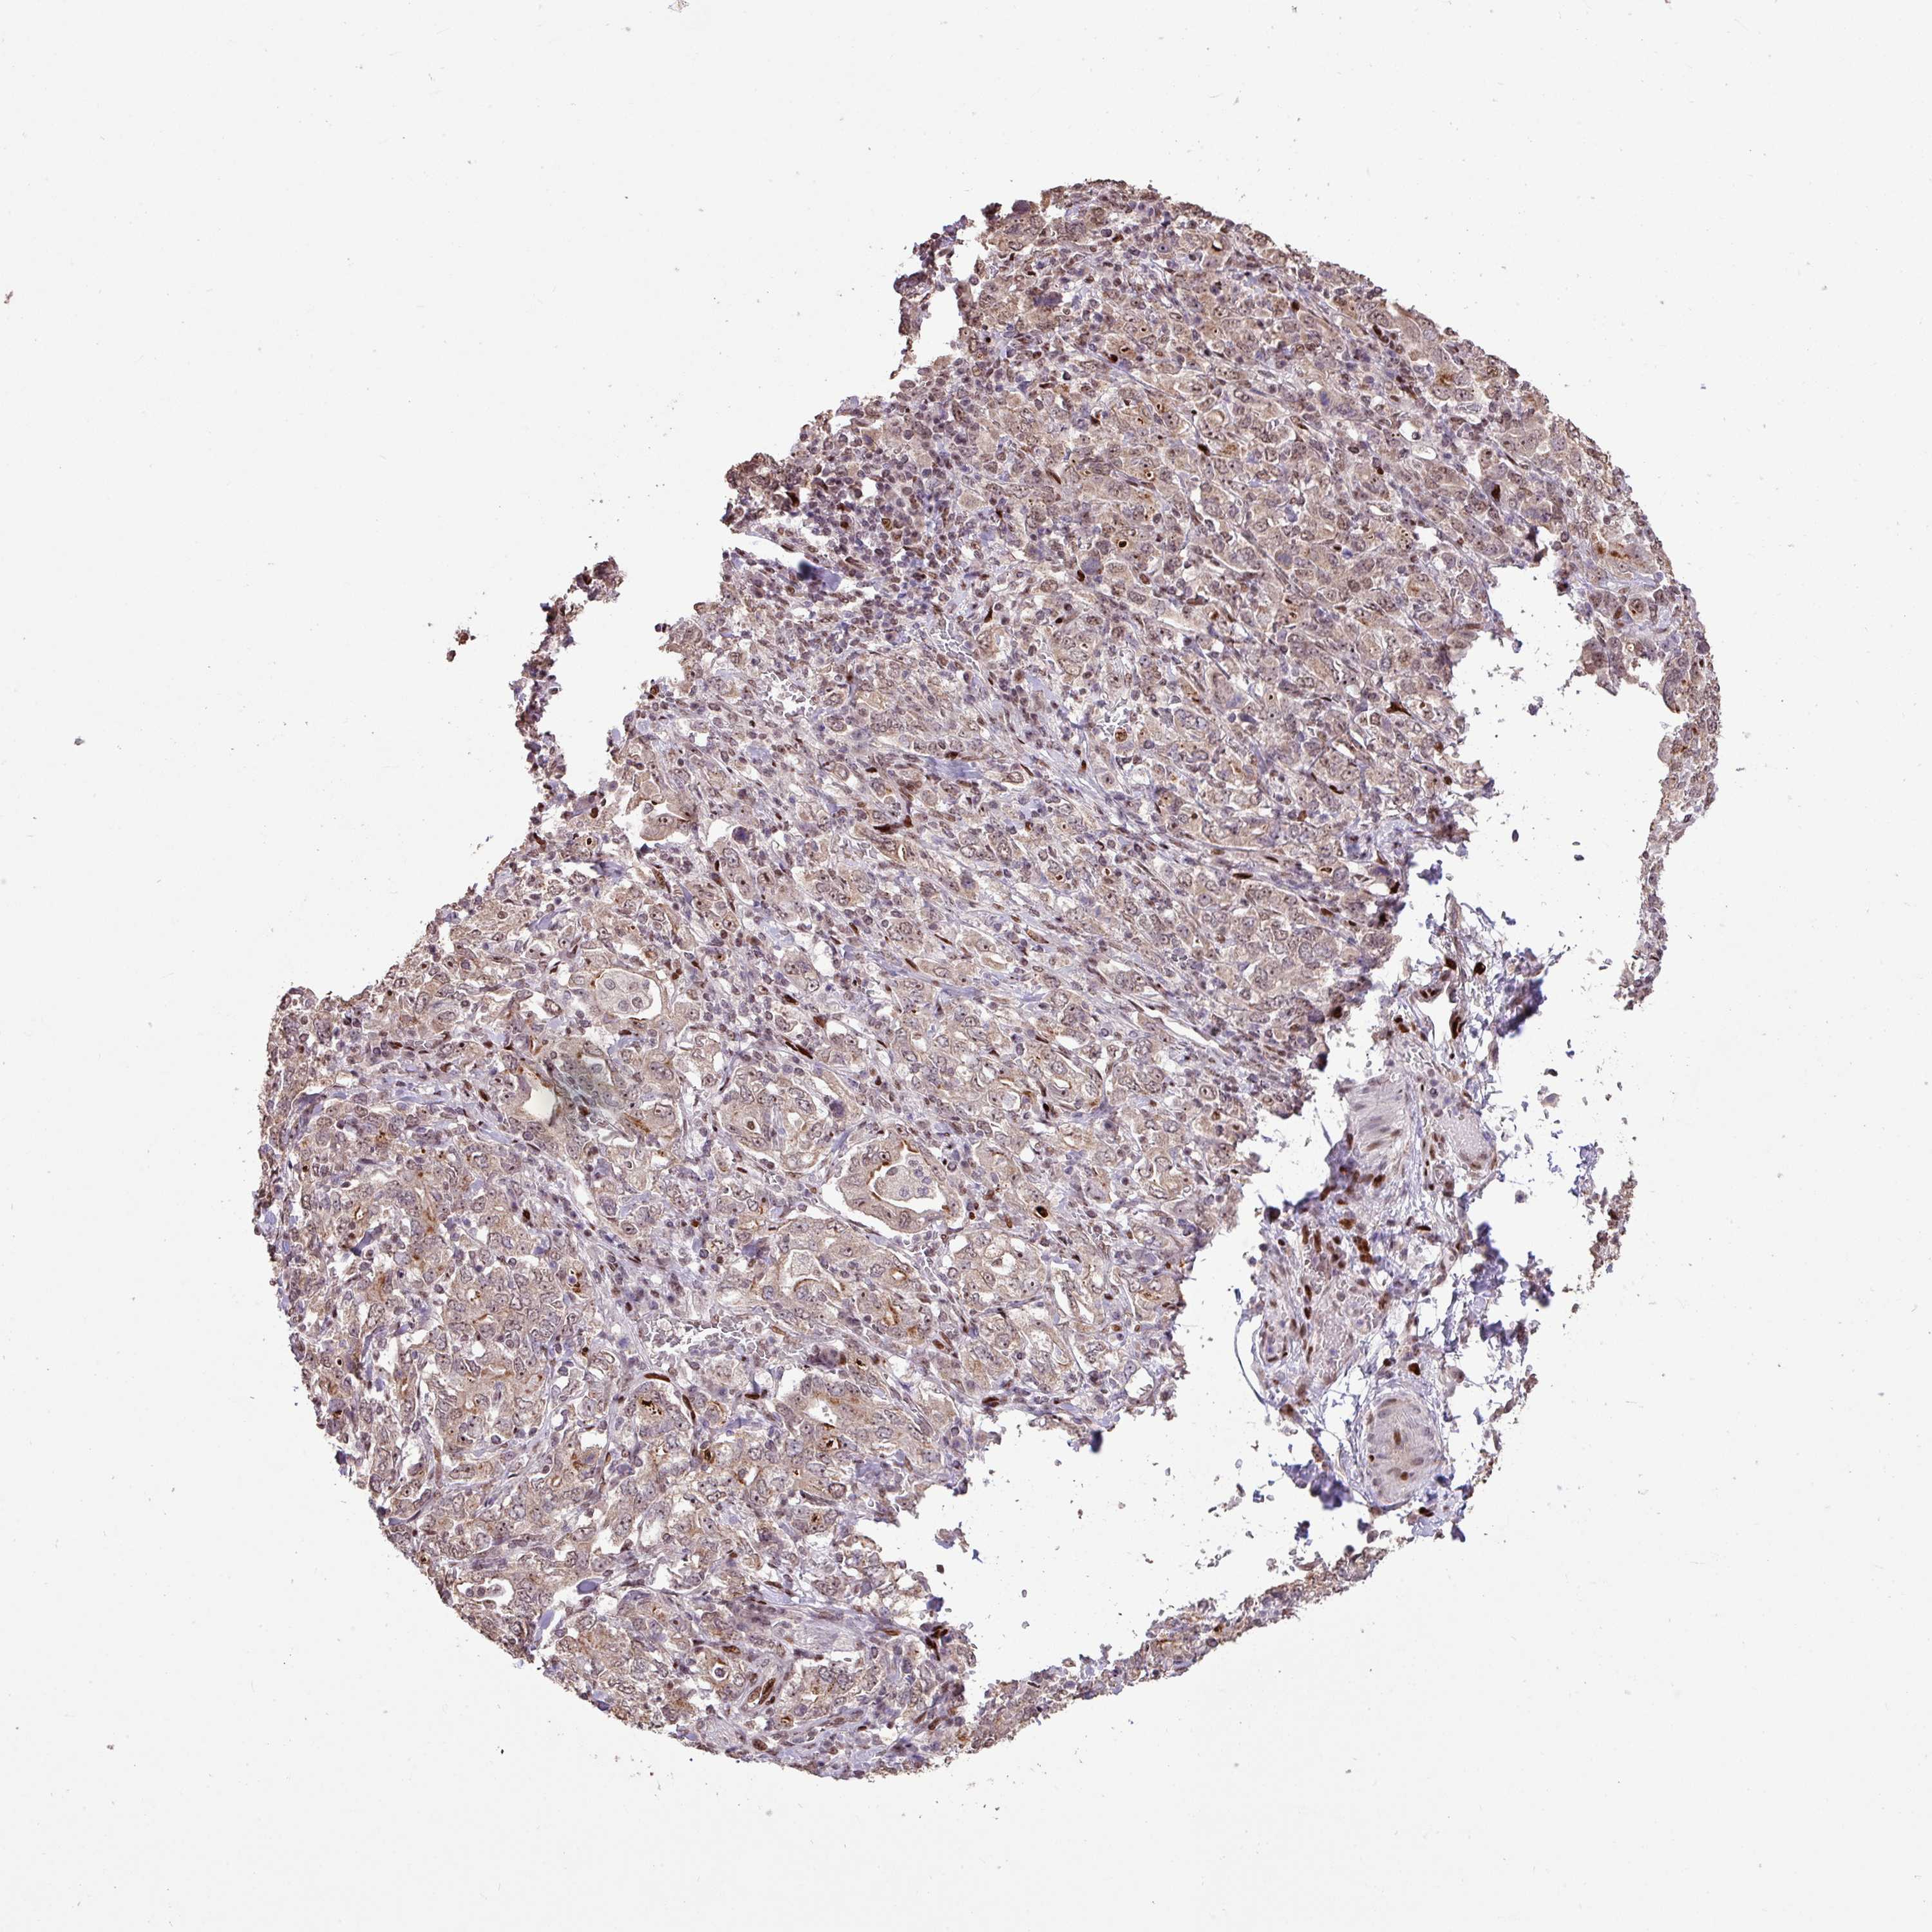

STOMACH CANCER - Protein expressioni

A mouse-over function shows sample information and annotation data. Click on an image to view it in a full screen mode. Samples can be filtered based on level of antibody staining by selecting one or several of the following categories: high, medium, low and not detected. The assay and annotation is described here.

Note that samples used for immunohistochemistry by the Human Protein Atlas do not correspond to samples in the TCGA dataset.

Antibody stainingi

Antibody staining in the annotated cell types in the current human tissue is reported as not detected, low, medium, or high, based on conventional immunohistochemistry profiling in selected tissues. This score is based on the combination of the staining intensity and fraction of stained cells.

Each image is clickable and will lead to virtual microscopy that enables deeper exploration of all samples and also displays staining intensity scores, fraction scores and subcellular localization as well as patient and tissue information for each sample.

Antibody HPA053153

Staining

High

Medium

Low

Not detected

Intensity

Strong

Moderate

Weak

Negative

Quantity

>75%

75%-25%

<25%

None

Location

Nuclear

Cytoplasmic/membranous

Cytoplasmic/membranous,nuclear

Adenocarcinoma, NOS